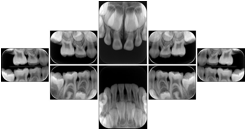

- OO-1. Intra-oral Full Mouth Series Structured Display

- OO.1.1-1. Hanging Protocol Names for Dental Image Layout based on JSOMR classification